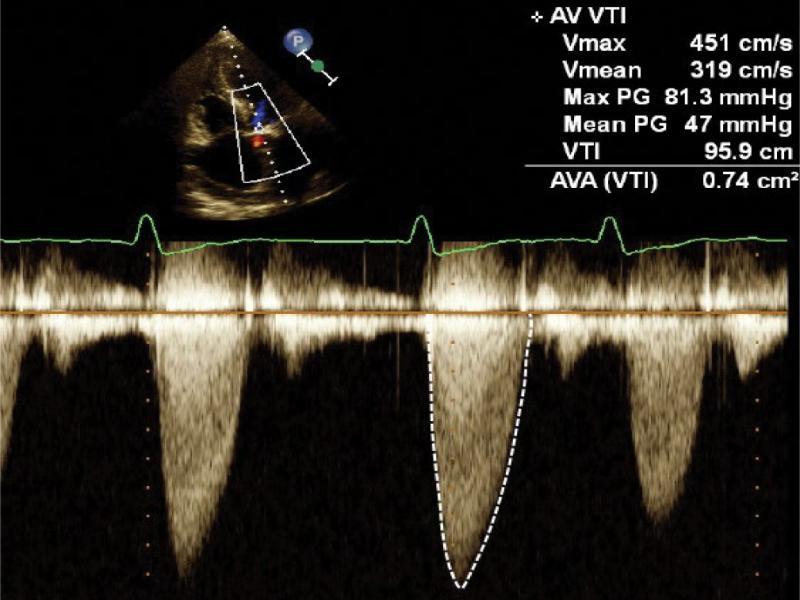

Aortic valve stenosis is usually caused by degenerative changes in the form of fibrosis and calcifications, which result in restricted mobility of the cusps. Continuous wave Doppler shows turbulent, rapid flow through the stenotic valve. The stage of aortic stenosis may be assessed based on the measurements of the peak velocity and the maximum/medium gradient, as well as planimetric calculation of the valve area or by using continuity equation from spectral Doppler recordings combined with the measurement of the left ventricular outflow tract width (Fig. 3). Stages of aortic stenosis are presented in Tab. 2.

Aortic stenosis. Flow spectrum in continuous wave Doppler. Peak velocity (Vmax), peak gradient (max PG) measurements, and aortic valve area (AVA) measurement using the equation of continuity are displayed